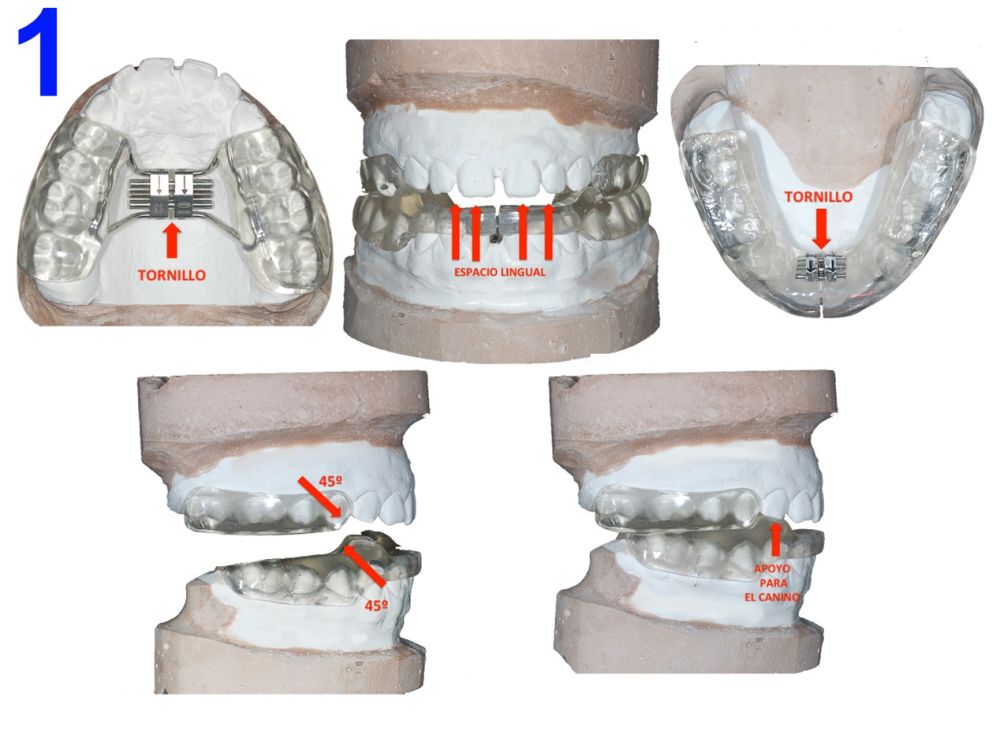

La colaboración de la Dra. Silvia Luckow fue decisiva tanto para el inicio de la actividad como para la modificación del diseño original del aparato. Se han realizado cambios en determinadas áreas específicas (Figura 1), con la intención de mejorar la efectividad, impedir efectos no deseados y facilitar el trabajo clínico. Las mencionadas modificaciones junto con la descripción exhaustiva de los tratamientos de ocho pacientes quedaron reflejadas en la publicación del libro «Twin Block Modificado», en el año 2016, por parte de Omar Maximino Milia2.

La parte superior del dispositivo, por su diseño, no podía ser cementada en la boca del paciente. Fue modificada utilizando el diseño del disyuntor original de McNamara, que presenta unas goteras dentarias que permiten la inclusión del cemento, y un tornillo tipo Hyrax para dar expansión o realizar disyunción, según se desee un efecto dentoalveolar o dentoesqueletal respectivamente.

Las modificaciones de la parte inferior del dispositivo son numerosas y apuntando a efectos concretos; se agregó un tornillo transversal para permitir expansión dentoalveolar, y también para dar «ajuste» cuando por el uso los dientes ceden y el aparato pierde retención. Se ha cubierto toda la arcada, con el fin de evitar la proinclinación de los dientes anteriores e inferiores por efecto de los planos inclinados combinado con la mordida constructiva. Delante de los planos inclinados inferiores, se crearon puntos de apoyo para los caninos superiores, para permitir realizar el movimiento de las guías caninas a ambos lados y contribuir al efecto del Ángulo Funcional Masticatorio de Planas3. Respecto al criterio de inclusión de la población estudiada, ha sido determinado de la siguiente manera: